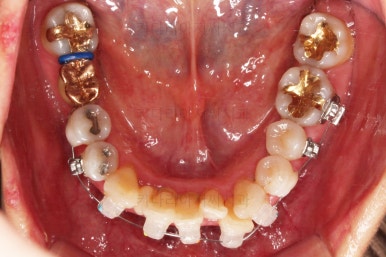

동래임플란트교정 초진 시 입안의 모습입니다.

치열이 전반적으로 삐뚤어져 있는 양상이고요.

아랫니가 윗니보다 더 많이 삐뚤어 있는데요.

유치 잔존

말그대로 어릴 때 빠져야 할 유치가 남아있다는 뜻인데요.

앞니 사이에 뾰족하게 남아있다 보니 자리만 많이 차지하고 있는 모습이었고 다른 영구치를 더 삐뚤게 만들었어요.

딱히 영구치가 모자라진 않는데 유치가 잔존하는 굉장히 드물고 독특한 상황이었습니다.